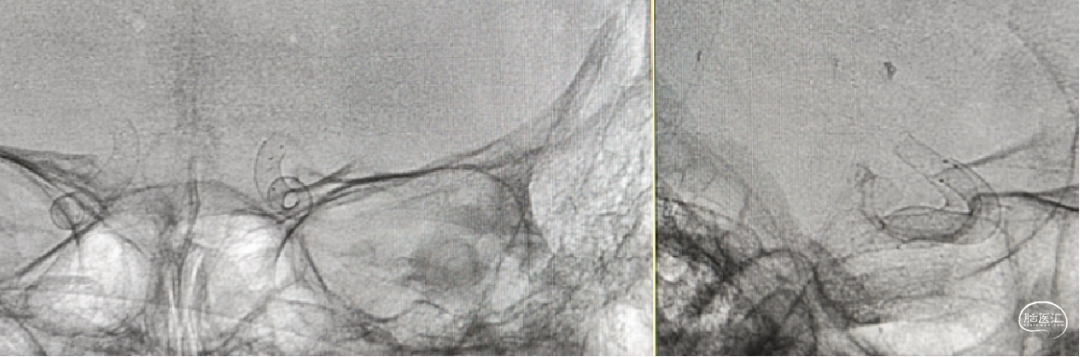

通桥微导丝导引支架管到位

支架鞘置入Y阀高压快速水化

支架释放过程(4倍速),重点是过弯推拉。

支架精显